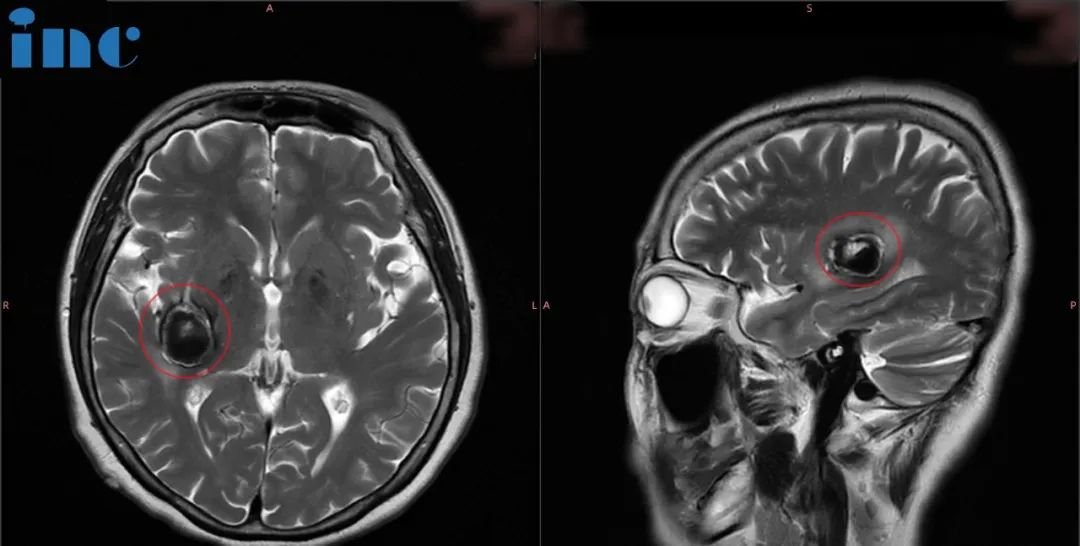

01、68岁罹患基底节海绵状血管瘤,手术会导致瘫痪失语吗?

病史摘要:“我们是从北京过来的,”巴教授6月中国行期间,一位68岁右侧基底节占位-海绵状血管瘤的柯女士通过INC咨询来到巴教授苏州独墅湖医院咨询室。“症状主要还是从头部、胳膊到后背,腿一直到脚底麻的感觉,偶尔脸部也会麻木……复查时发现病灶变大了,原来是18*19mm,现在是24*19mm;而且还多次出血。”因症状加重,病灶增大,问诊多名神经外科医生,两个专家团队医生给出了截然不同的意见:不赞成手术治疗,理由是年龄大,手术导致瘫痪失语的风险大。另外一个医生团队的意见是现在可以马上手术,但效果不确定。因此柯女士至今尚未进行治疗。

“血管畸形有可能会变大,也有可能会变小!如果血管畸形变大出血多,内囊的区域主管我们手脚的运动,患者就可能出现偏瘫。经过影像的对比,75%支持手术,25%支持可以再观察。如果症状加重,就需要治疗。要是真的等到偏瘫了再手术,那偏瘫恢复的机率要比现在要小很多。当然这个血管畸形是可以很好的切除的。”

但是由于害怕手术,还是选择了保守治疗,等待巴教授下次来华。得知巴教授9月下旬来华的消息后,柯女士再次请巴教授为她远程评估。巴教授表示:对比2023年6月和2022年7月影像发现,现在的血肿仍然比去年大。我仍然认为从长远来看,手术对病人来说是更好的选择,但我不能说手术是需的,我可以完全(全切)切除出血性病灶。我早在20年前就公布了此类手术的技术和结果,并在此后为各种年龄段的病人成功实施了无数次手术。因此,她不应该对此感到害怕。因此,当我为这名患者进行手术时,她不会出现长期性偏瘫!在较坏的情况下,她的左侧可能会有轻微的无力感,但如果真的出现这种情况,也会在接下来的几周内恢复正常。